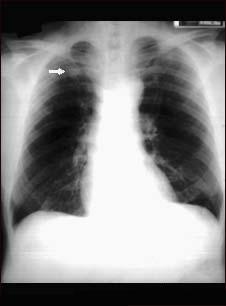

Hemoptizia (expectoratia cu sange)